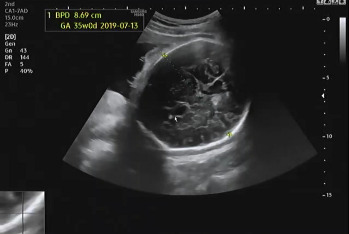

진료 순서가 되어 복부 초음파를 확인하였다. 여전히 햇님이는 자신의 건강함을 알리기 위해 초음파를 보는 내내 손을 이리저리 움직였다. 머리둘레, 복부둘레, 허벅지 뼈 길이를 측정하여 대략적인 체중을 확인하고 태아가 주수에 알맞게 크고 있는지를 확인했다. 머리둘레는 35주 차, 복부둘레는 34주 5일, 허벅지 뼈 길이는 33주 4일이라서 이상하다 생각했는데 평균적 수치는 주수에 알맞게 성장이라는 것을 듣고 안심했다. 2주 뒤인 37주 차에 내원을 예약했다.